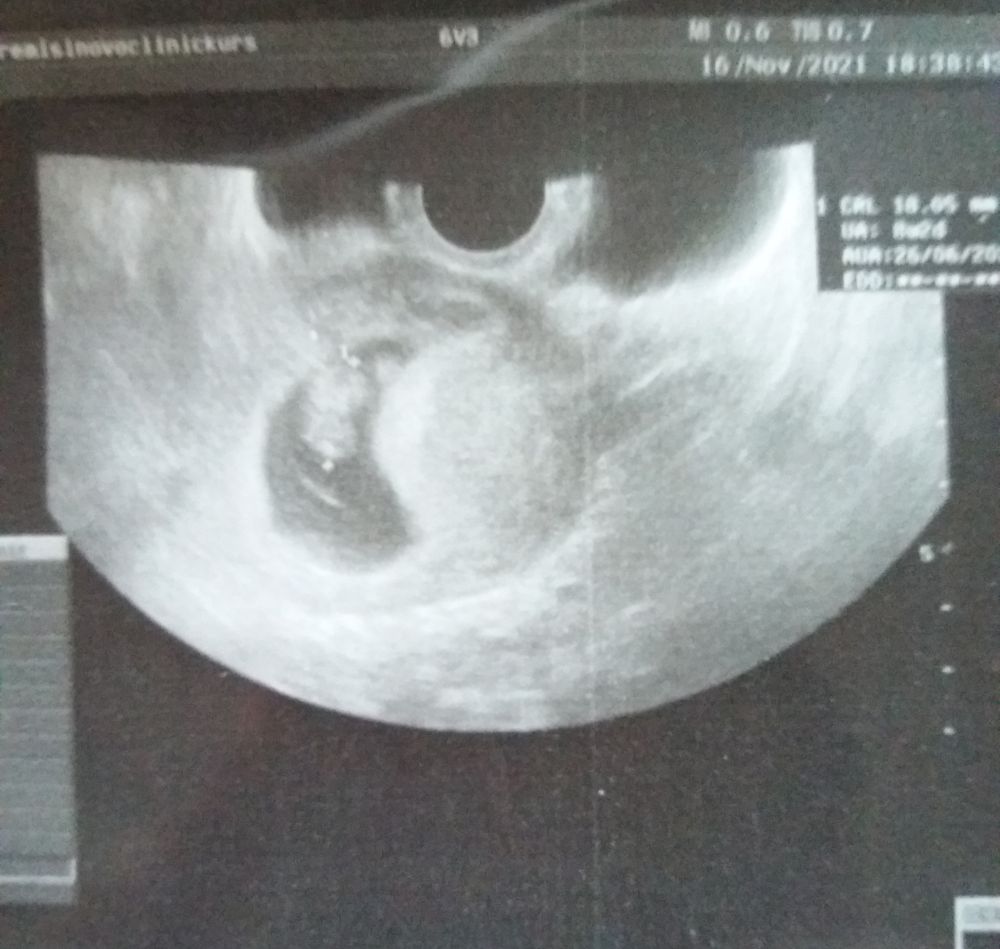

Первое фото бусинки🤰

У нас получилось! Я беременна!

Она такая кроха🤗😍